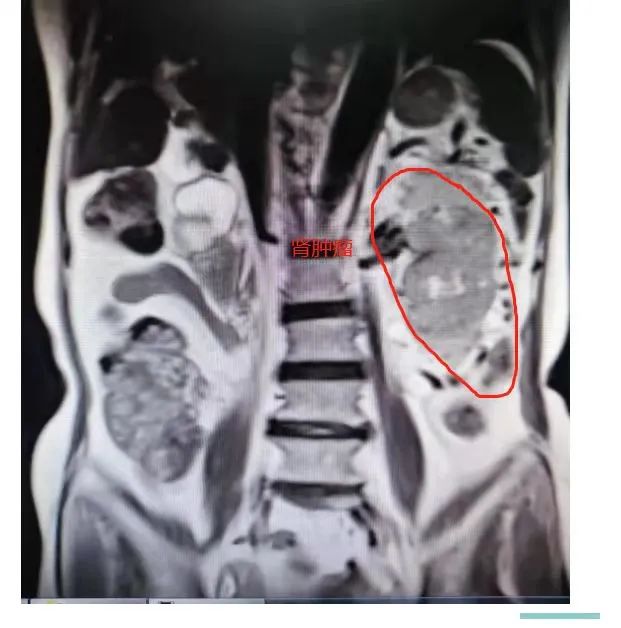

原来,在12月25日,86岁高龄的卿奶奶因突发血尿,到河池市人民医院泌尿外科就诊,经过一系列检查,确诊为:左肾透明细胞腺癌。根据卿奶奶的临床表现、体征及辅助检查,考虑恶性可能较大,保守治疗无效,需要进行手术治疗,因肿瘤较大,且卿奶奶合并有肾周感染、支气管炎、高血压、贫血、肠粘连等疾病,给手术增加了难度。

卿奶奶术前肾内肿瘤CT情况